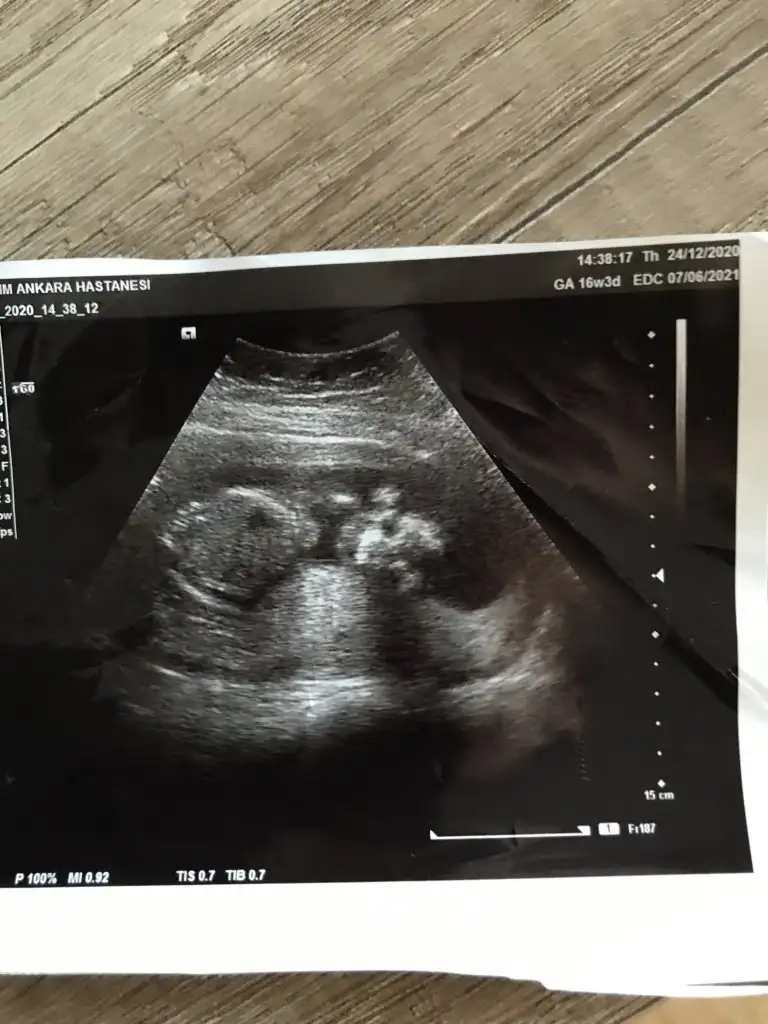

• IMG_20201209_175934.webp

IMG_20201209_175934.webp

22,1 KB · Görüntüleme: 79